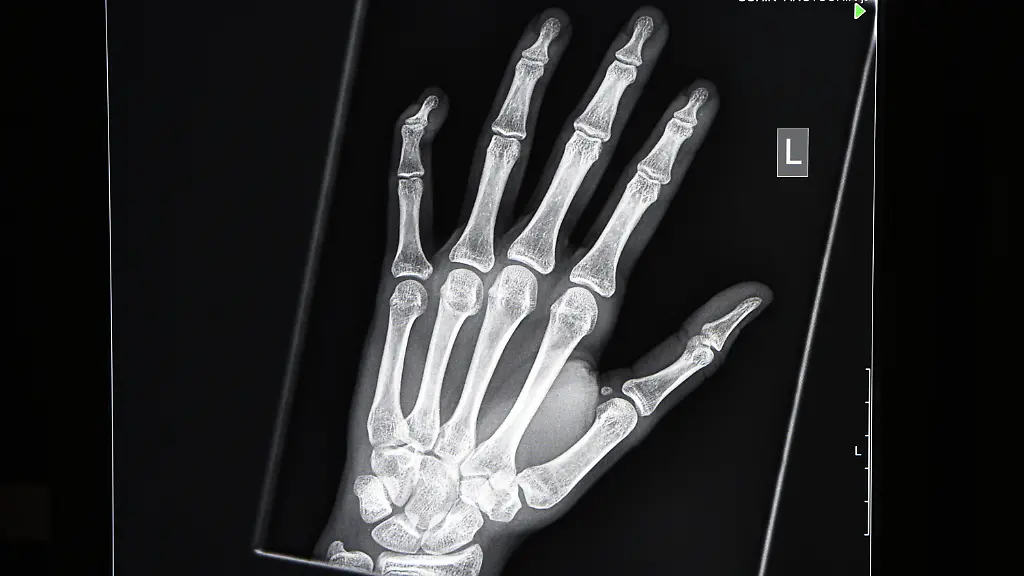

Wie die "taz" nun berichtet, werden in Hamburg neben Panoramaschichtaufnahmen der Kieferknochen und Röntgenbilder von Handskelett noch weitere, fragwürdigere Methoden zur Altersfeststellung praktiziert.